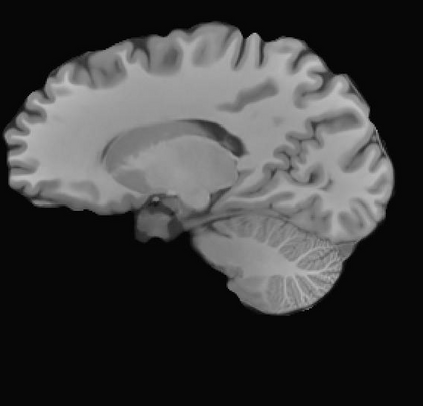

Magnetic resonance (MR) images are often acquired in 2D settings for real clinical applications. The 3D volumes reconstructed by stacking multiple 2D slices have large inter-slice spacing, resulting in lower inter-slice resolution than intra-slice resolution. Super-resolution is a powerful tool to reduce the inter-slice spacing of 3D images to facilitate subsequent visualization and computation tasks. However, most existing works train the super-resolution network at a fixed ratio, which is inconvenient in clinical scenes due to the heterogeneous parameters in MR scanning. In this paper, we propose a single super-resolution network to reduce the inter-slice spacing of MR images at an arbitrarily adjustable ratio. Specifically, we view the input image as a continuous implicit function of coordinates. The intermediate slices of different spacing ratios could be constructed according to the implicit representation up-sampled in the continuous domain. We particularly propose a novel local-aware spatial attention mechanism and long-range residual learning to boost the quality of the output image. The experimental results demonstrate the superiority of our proposed method, even compared to the models trained at a fixed ratio.